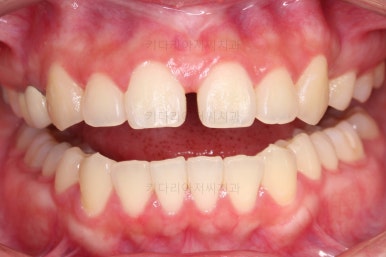

전후 비교해 볼게요.

임플란트 하러 오신 분을 임플란트 없이 마무리 했고요.

젊으신 나이에 임플란트를 하기 보다는 약간의 시간을 더 투자해서 이렇게 마무리를 하는게 여러모로 합리적인 치료였습니다.

환자분이나 부산치아교정도 만족스러운 치료였습니다.